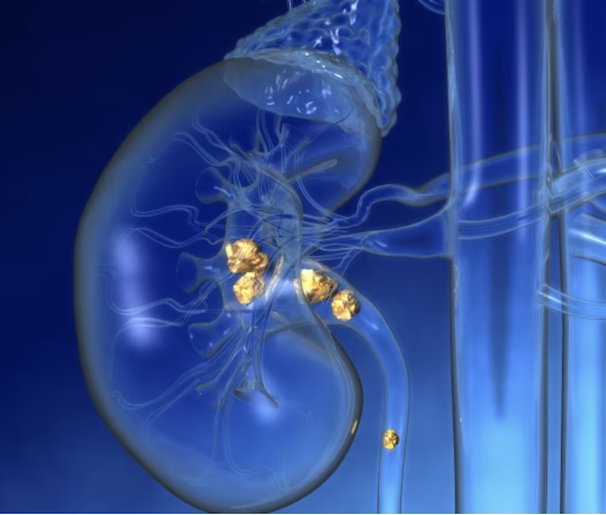

Kidney stones are common, affecting about 10% of people at some point, according to the National Kidney Foundation. Often, they can be passed in the urine. But if a large stone causes a urine blockage or too much agony, doctors may need to remove it.